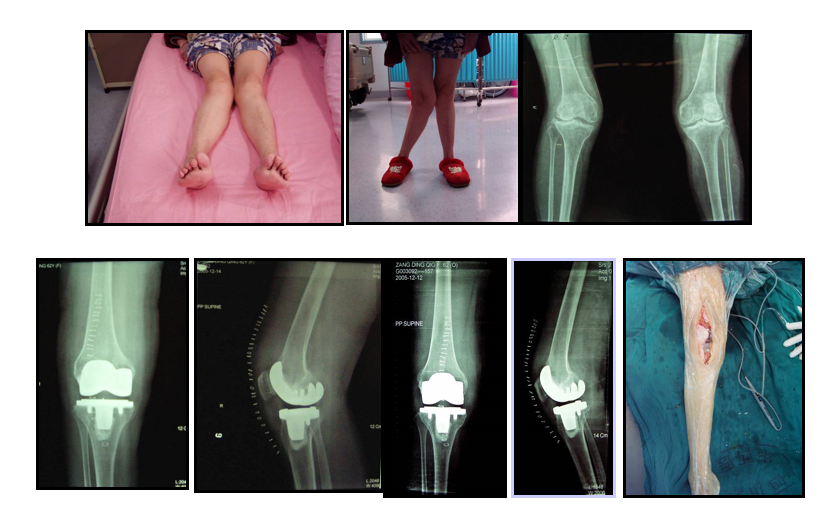

膝关节外侧常有手术时,包括外侧副韧带、股二头肌腱破坏。

此型外翻畸形采用人工膝关节置换必须慎重。

术前确定切骨线,胫骨上端切骨线为0°。外侧平台尽量切薄,而内侧平台则切骨很厚。

在膝关节翻修术中,部分限制型假体适用于通过软组织松解等手段能获得膝关节伸屈间隙和内外侧平衡、骨缺失不明显、骨质较好时。

胫骨侧加粗加高的中央柱和股骨侧加宽加深的髁间凹槽相匹配,控制内外翻稳定,可部分代偿侧副韧带功能

常用于存在骨缺损和关节不稳的翻修手术

建议加用髓内柄以获得更高的稳定性